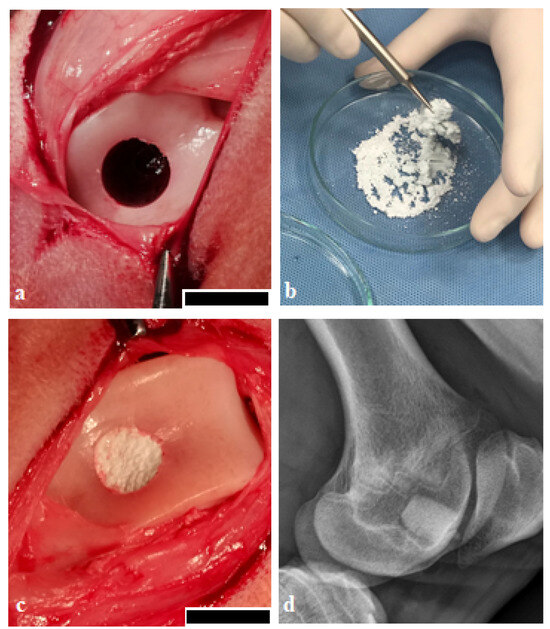

Radiological examination confirmed that the process of biodegradation of biocements was incomplete, and biomaterials were only partially resorbed. Unresorbed biomaterials appeared radiodense on both X-ray and CT images (Figure 5). Remnants of both biocement systems were present in the trabecular bone. The subchondral bone was intact. The area around the defect was homogeneous, without pathological irritation, and without osteolytic changes. The new bone was attached directly to the surface of the material, with no free spaces, gaps, or fibrous capsules between them. No swelling of the adjacent soft parts was present. We observed areas of less echogenic matter which verifies primarily the newly formed bone tissue. CT findings indicate good healing of the defects without any signs of irritation (Figure 5).

Figure 5.

X-ray, CT, and MR imaging. (a) X-ray examination of the osteochondral defect after treatment with biocement CX; in trabecular bone, the unresorbed biocement was firmly attached to adjacent bone tissue, no gap and no pathomorphological changes were observed; (b) X-ray after treatment with biocement C; no signs of tissue irritation were observed; (c) untreated defect; new bone formation is absent; (d) MRI, treatment with biocement CX; the treated defects were completely filled with the newly formed cartilage to the expected level equal to the adjacent cartilage, and tissue surface was smooth, well-defined. (e) MRI, treatment with biocement C; newly formed cartilage had a comparable thickness to the adjacent tissue, slightly hyperintense areas were visible; (f) MRI of the untreated defect; the defect in its full extent shows hyperintense and hypointense signal alterations; (g) CT image, treatment with CX, partial degradation of biocement, unresorbed part of biocement was visible under the subchondral bone, the surface of biocement was covered with new bone tissue; (h) CT image, treatment with C, biocement was not completely degraded and resorbed, and integration of the biocement with the adjacent bone was confirmed; (i) untreated defect, the osteochondral defect was not completely covered by the newly formed bone, and a large cavity remains inside the bone; arrows: indicated areas of the healed defect.

X-ray images did not indicate the presence of pathological changes, like narrowing of the joint space, the formation of subchondral cysts, osteonecrosis, or osteophytosis in the investigated groups. Similarly, there were no signs of osteoarthritis. In most cases, the new bone tissue in the untreated defects was only partially visible and was formed closer to the bone surface up to a maximum thickness of 2.5 mm, but the bone defects were not completely filled by newly formed bone. In a few cases, several defects were without any new trabecular bone formation.